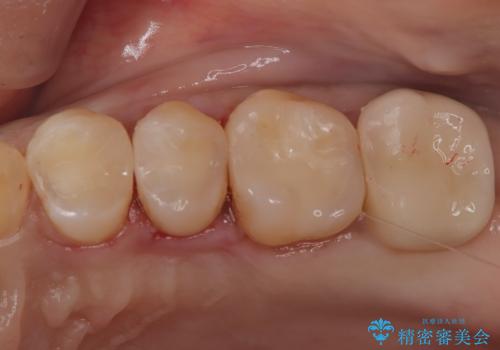

【セラミックインレー】虫歯の治療

- 定期検診にて虫歯を認めたため、セラミックインレーにて治療を行いました。

治療時にはラバーダムを装着しております。